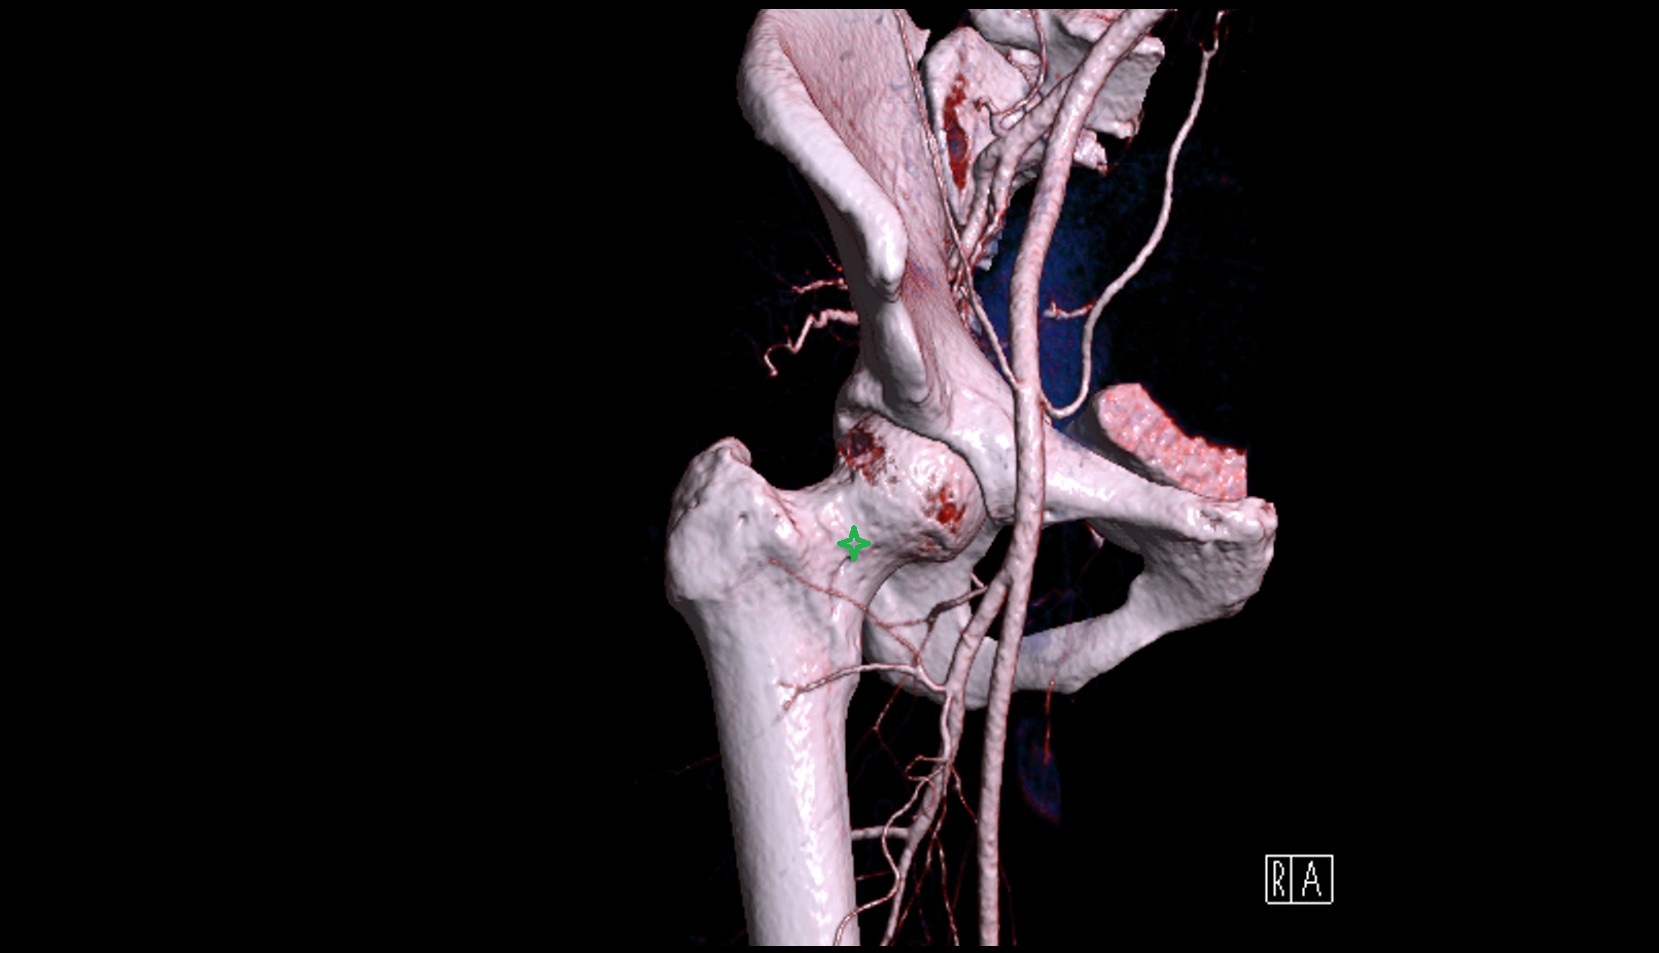

- Head of femur

- Neck of femur

- Lateral circumflex femoral artery

- Deep femoral artery (profunda femoris)

- External iliac artery

- Femoral artery

- Internal iliac artery

- Medial circumflex femoral artery

- Obturator artery

- Superior gluteal artery

- Hip joint